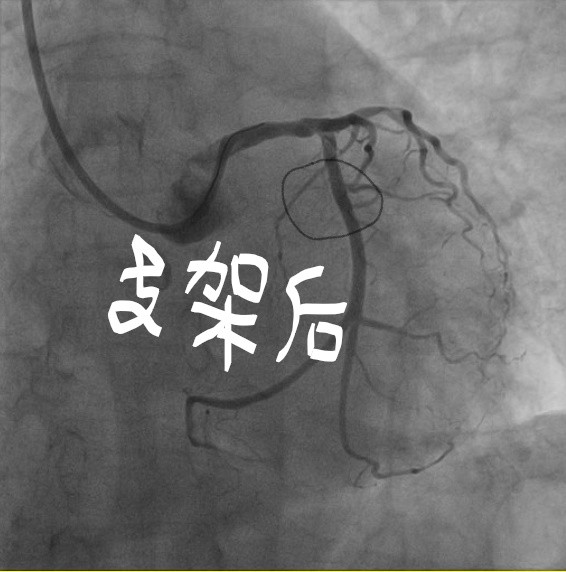

急性心肌梗死发病急、病情凶险、死亡率高,是导致中老年人猝死的主要原因之一,当高龄老人遭遇急性心梗时,凶险更是不言而喻。近日,我院心血管内科成功救治一名90岁高龄的心肌梗死患者,术后患者康复出院并送来锦旗。这是我院心肌梗死患者中年龄最大、成功完成急诊PCI手术的女性患者。

80岁以上的患者,因身体的各种功能明显衰退,行心脏支架植入术风险很大,几乎是手术的雷区。但如果不进行介入精准治疗,延误了最佳的治疗时机,心肌坏死情况可能会加重,随时有生命危险。心肌梗死猝死率较高,越早治疗,效果越好。